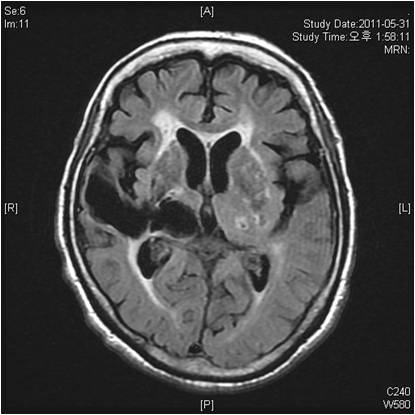

허혈성 뇌졸중은 발생 기전에 따라 대혈관 질환에 의한 뇌경색, 심인성 뇌경색 또는 심인성 뇌경색, 소혈관 질환 또는 틈새 뇌경색, 기타 드문 이유가 되는 것에 의한 뇌경색으로 나누어져요. 에피소드는 일정 기간 동안 증상이 완전히 가라앉는 경우입니다.

허혈성 뇌졸중의 대표적인 이유가 되는 것은 고혈압, 당뇨병, 고지혈증 등으로 인해서 뇌에 혈액을 전달하는 혈관에 동맥경화(동맥경화)가 발생하여 뇌로 가는 혈류를 차단하는 것입니다.